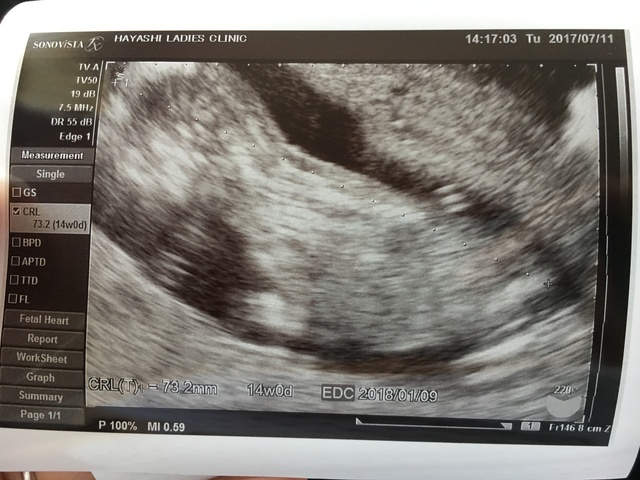

14週0日(14w0d・性別不明)|natsuki. さん(24歳)

エコー写真撮影時のエピソード:

3週間ぶりの検診で小心者の私のドキドキ、不安とは裏腹に前回の検診より成長しており一安心。初めて心音も聞かせてもらって、より一層実感が増しました。

内診中も凄い元気に飛び跳ねててかわいかったな。次の検診は4週間後なので今から楽しみ。